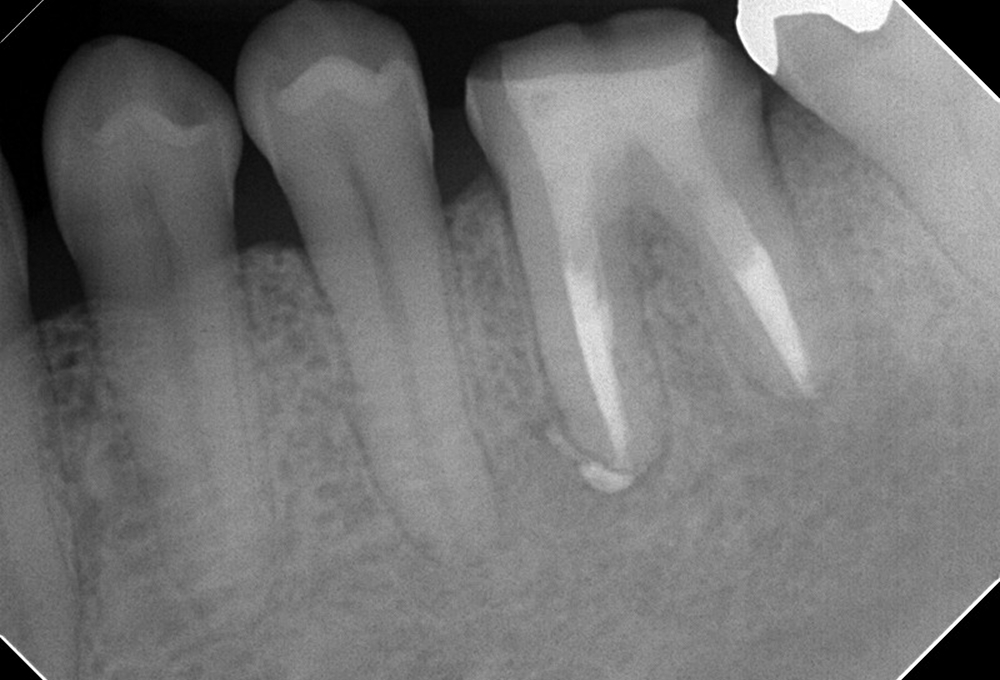

①術前 下顎小臼歯の根尖病変 未処置根管有

②根管充填後 未処置根管も治療 根尖病変も縮小した